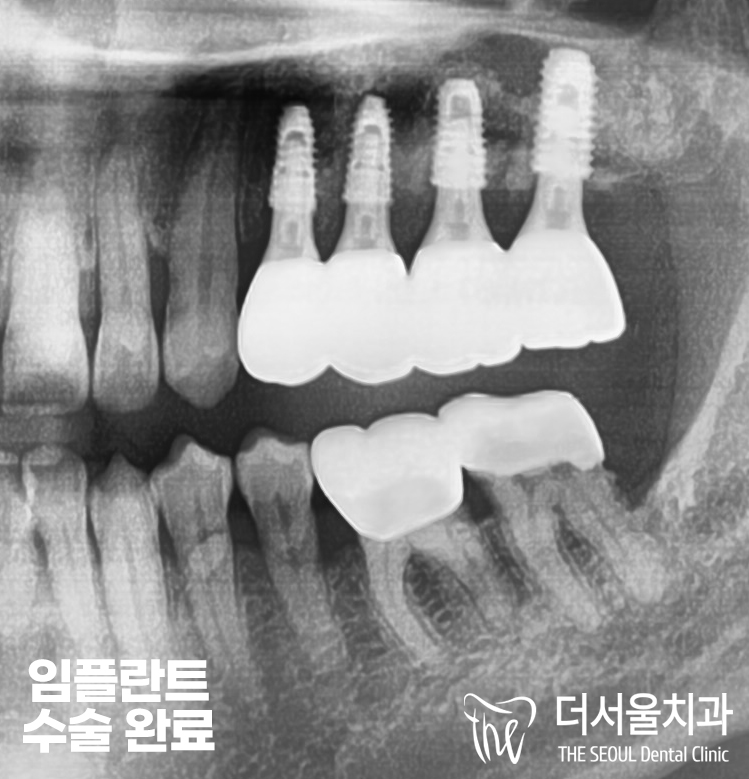

『수술 완료』

수진동치과 에서

24X27 위치에 임플란트 식립을

모두 마친 상태입니다.

안정감있게 잘 고정되었으며,

환자분 또한 불가능했던 수술이

좋은 결과로 이어짐에

만족하셨습니다.